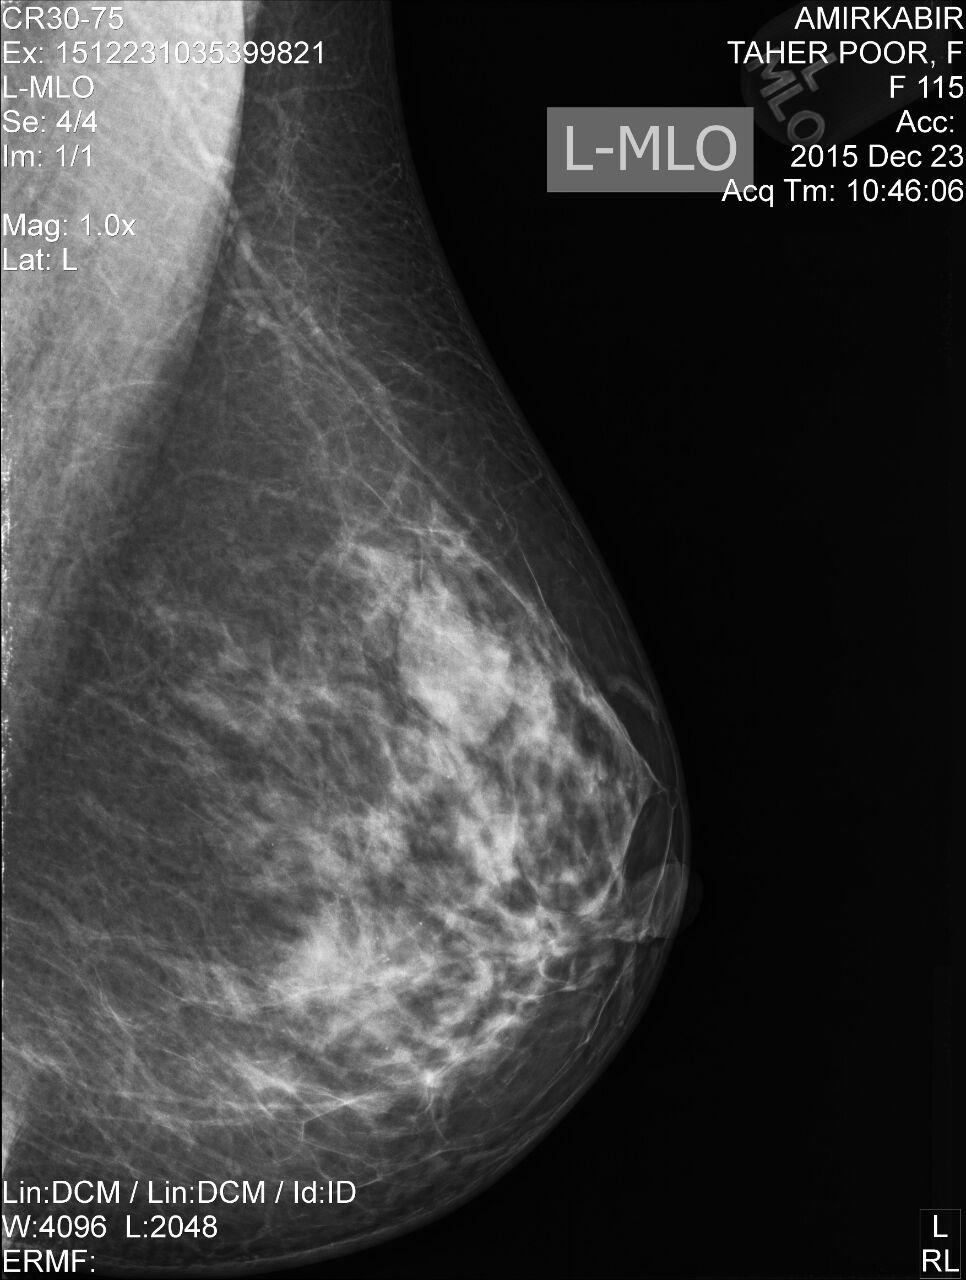

Mamography

Breast cancer